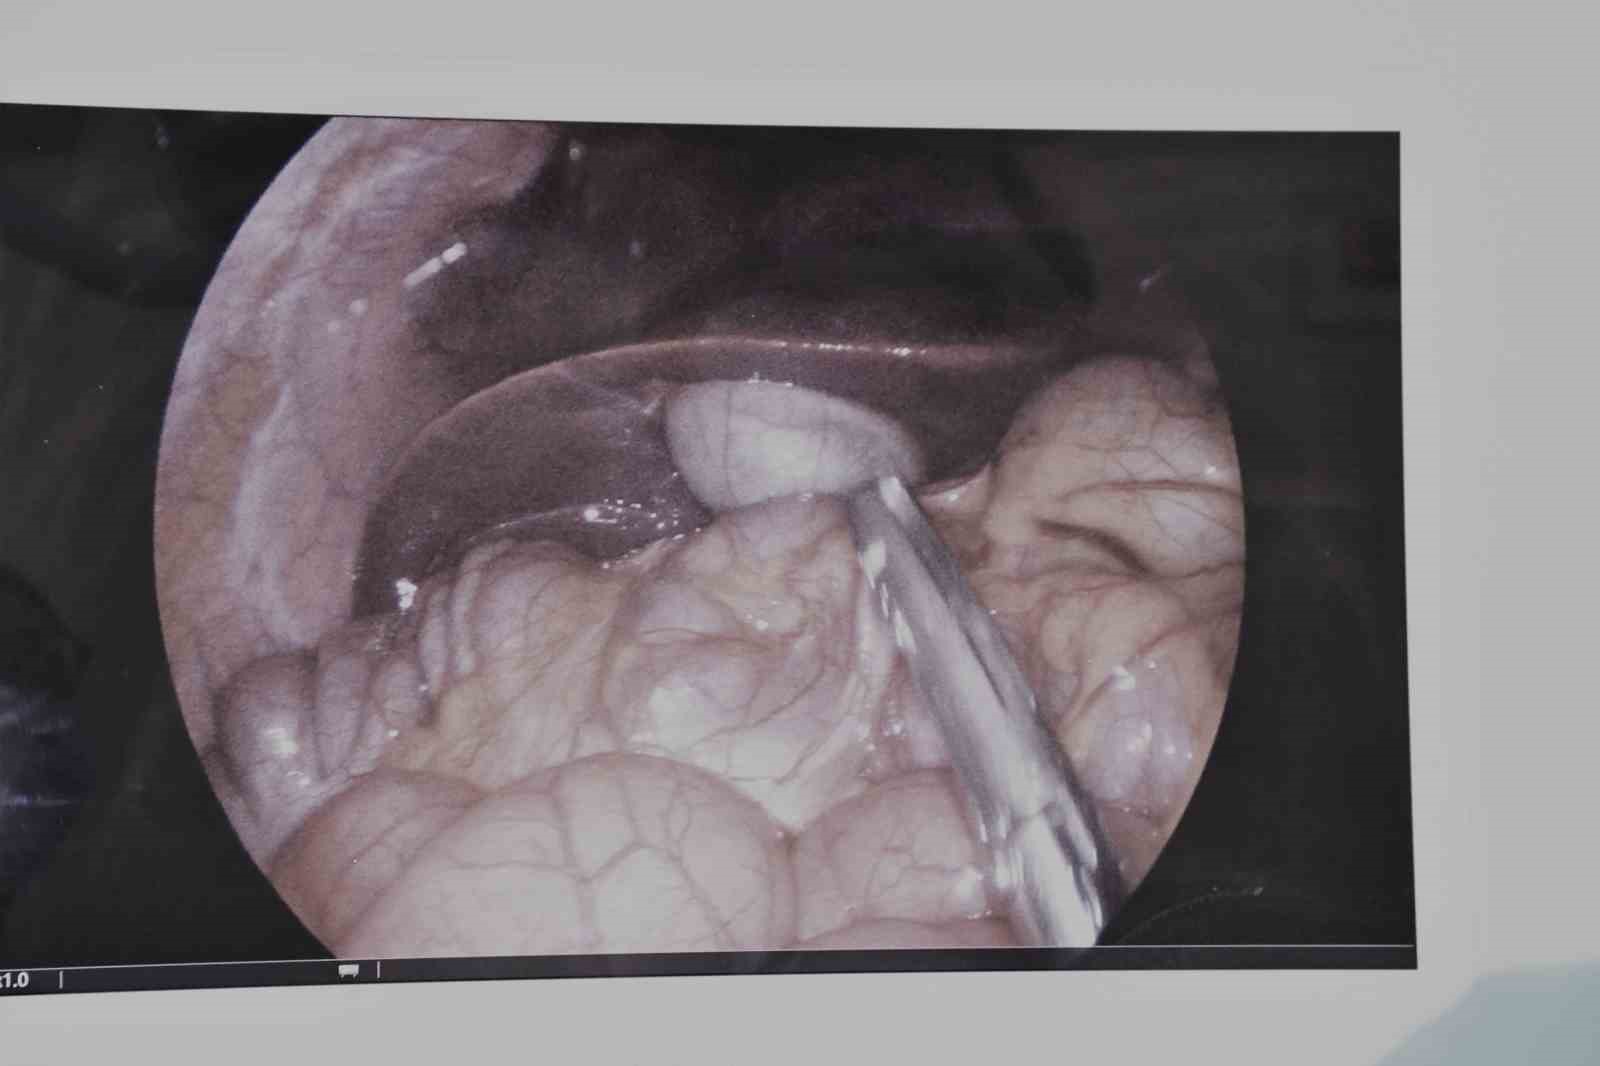

Operasyonu gerçekleştiren Çocuk Cerrahisi Uzmanı Op. Dr. Serkan Odabaşı, yaptığı açıklamada, hastanın uzun süredir karın ağrısı, mide bulantısı ve sindirim problemleri şikayetleri olduğunu belirtti. Dr. Odabaşı, yapılan detaylı tetkikler sonucunda safra kesesinde enfeksiyon tespit edildiğini ifade ederken, "Bu durumda en uygun tedavi yöntemi, safra kesesinin alınması yani kolesistektomi ameliyatıdır. Operasyonu kapalı (laparoskopik) yöntemle gerçekleştirdik. Laparoskopik cerrahi, karında büyük kesiler açmadan, küçük delikler aracılığıyla özel cerrahi aletlerle yapılan modern bir tekniktir. Bu sayede hastamızın ameliyatı başarılı bir şekilde tamamlandı. Hastamızın kısa sürede taburcu edilmesi planlanmaktadır” dedi.